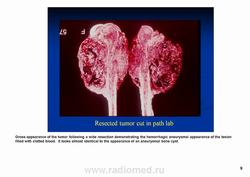

Телеангиэктатическая остеосаркома относится к остеолитическим вариантам обыкновенной интрамедуллярной остеосаркомы и содержит кистовидные сосудистые полости, разделенные тонкими костными перегородками. В некоторых случаях эта опухоль симулирует аневризматичесую костную кисту. Частота такого варианта составляет 0,4—12 % от общего числа остеосарком. Патологический перелом к моменту диагностики встречается более чем у 25 % больных, тогда как лиц с обыкновенной остеосаркомой — не более чем 5 %. У пациентов старшей возрастной группы, а также лиц с поражением костей осевого скелета развитие телеангиэктатической остеосаркомы происходит на фоне болезни Педжета. Макроскопически эта опухоль имеет вид то крупного сгустка крови или некротической массы, то многокамерной кисты, содержащей жидкую кровь, как это бывает в аневризматической костной кисте.

Макроскопически ткань геморрагична; редко встречаются плотные «мясистые» поля.